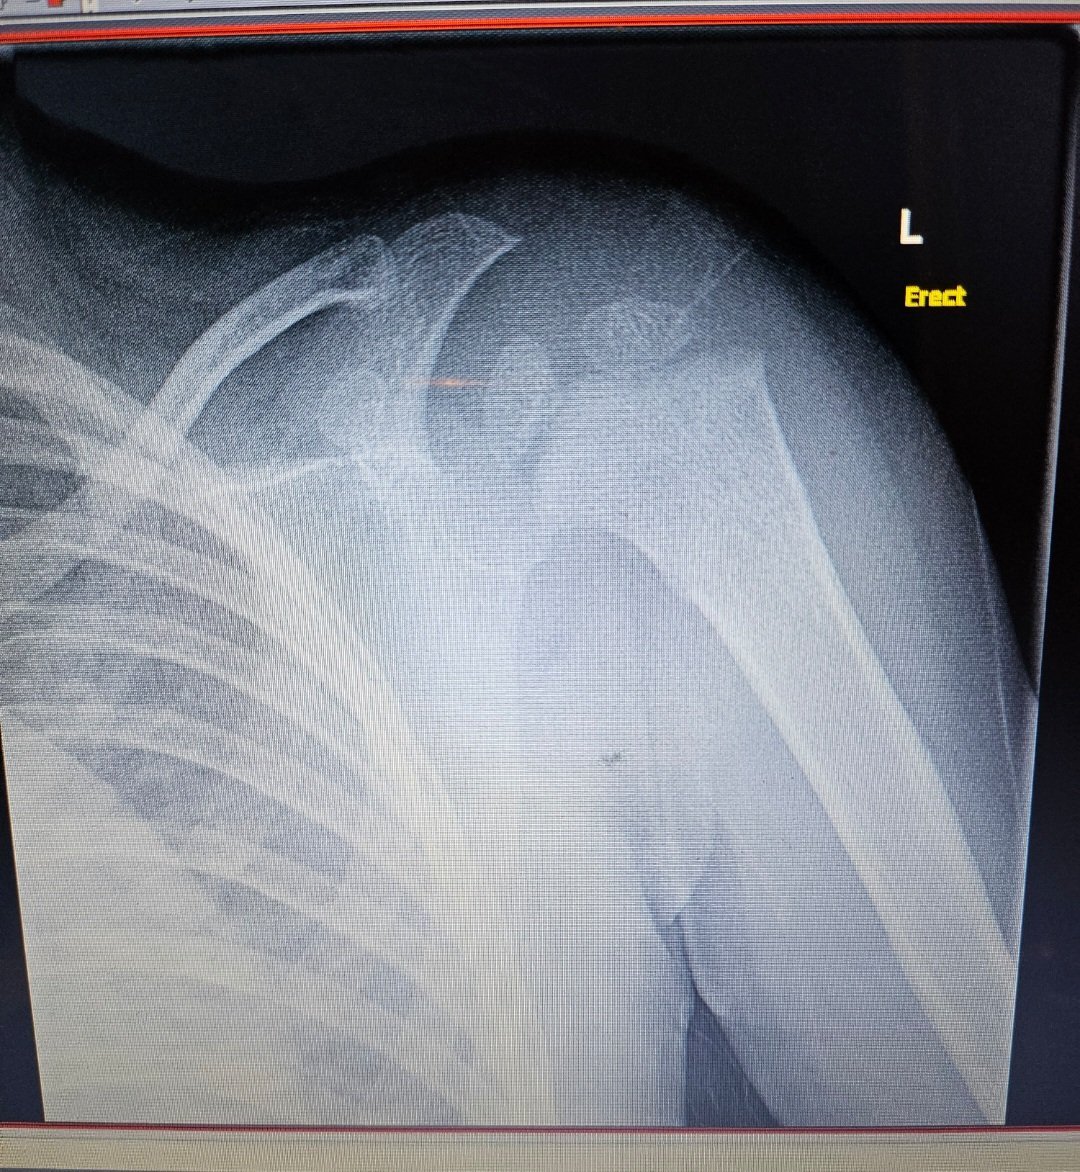

Какво е препоръчителното лечение за частична руптура на сухожилието на m.supraspinatus при раменна травма?

Пробвайте физиотерапия и рехабилитация